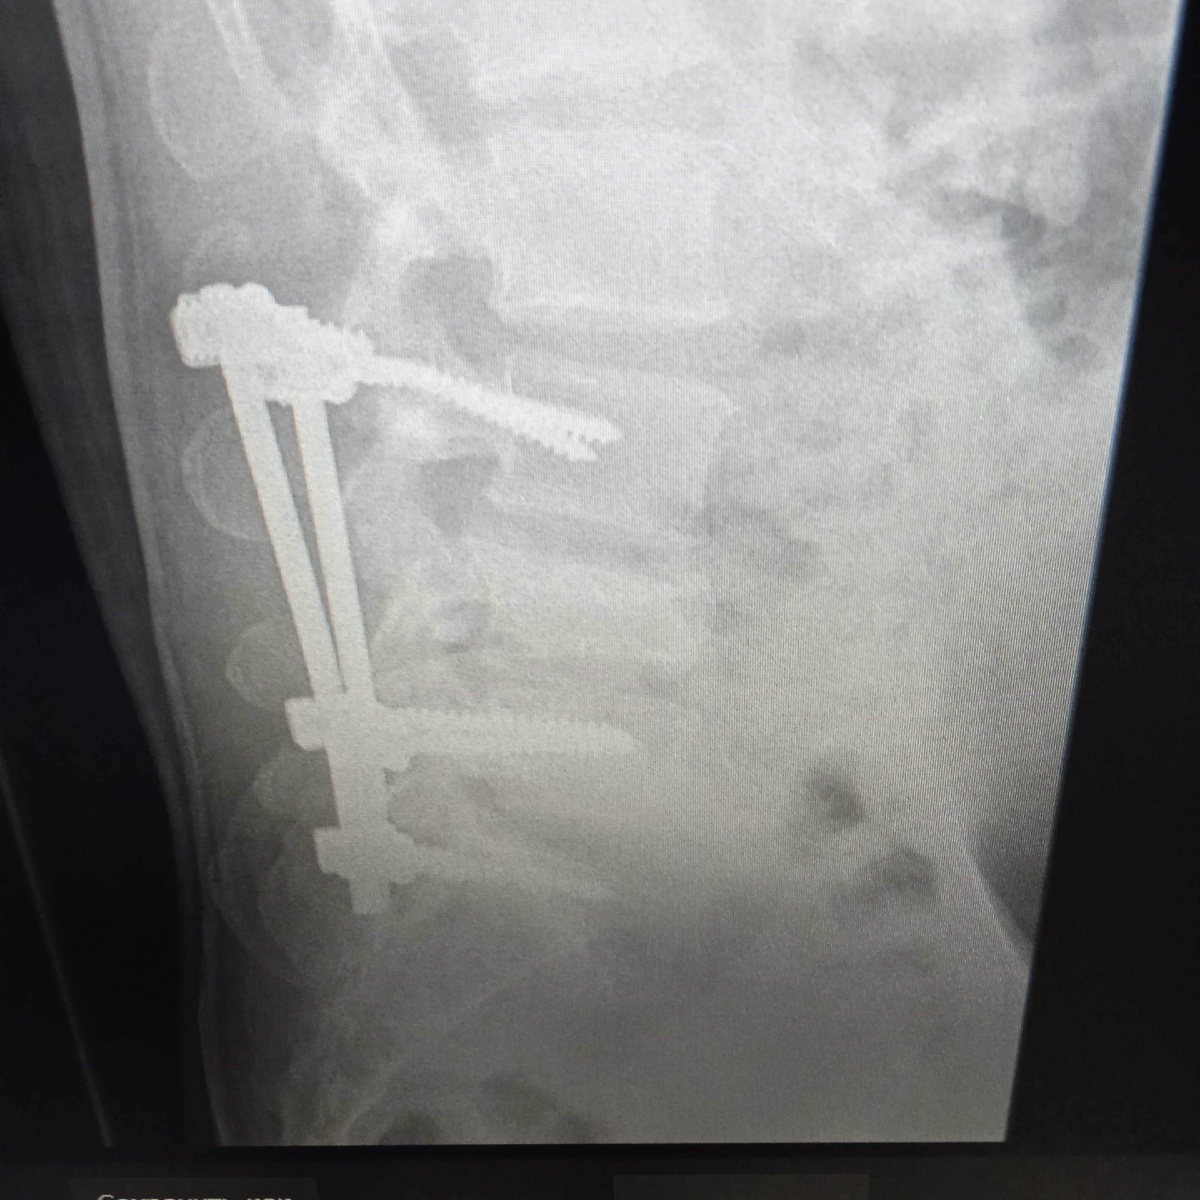

На снимке вот что:

Боковая

А случился у него, выражаясь на медицинском дебриколяж (разрушение)металлоконструкции.

Пациенту в прошлом году была выполнена транспедикулярная фиксация тел позвонков. Конструкция представляет собой такую "штангу" с креплениями на шляпки винтов. И вот эти самые шляпки и оторвались, оставив винты в позвонках.

Их больше не вытащить, это точно, они так и останутся в телах позвонков.